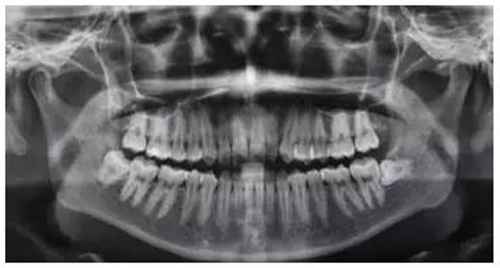

圖1.術(shù)前的患者的全景片影像檢查:48合面平齊區(qū)7牙頸部。

(1)根據(jù)全景片影像檢查:48牙冠合面平齊牙頸部,但牙根未完全發(fā)育完成,患者年紀(jì)尚小,屬于最佳拔牙年齡。故采用小切口,不附帶垂直切口